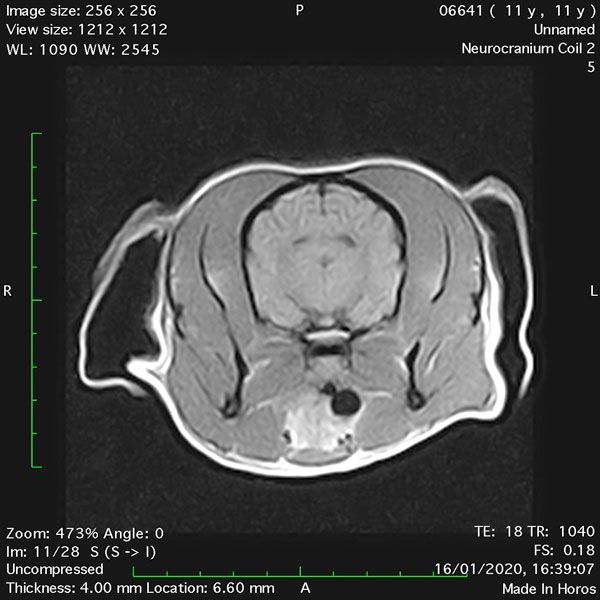

- Transverse T1 – Spin Echo T1 (Figure 1);

MRI images were viewed in DICOM format (Digital Imaging and Communications in Medicine) (Figures 1-7) and assessed in-house under the guidance of a board-certified radiologist. The series were evaluated for changes in intensity in the T1- and T2-weighted sequences (T1w and T2w, respectively). There was a 4mm x 7mm x 7mm intra-axial, wedge-shaped hyperintense reasonably-well demarcated region in the right cerebrum visible in the T2w images (Figures 2-3). This was consistent with a focal infarct. No contrast enhancement, anatomical abnormality nor space occupying lesion was noted in the T1w sequences (Figure 1, Figure 4). There was no observed pathology on assessment of the FLAIR images (Figure 5).

Figures 1-7: Images obtained with MRI depicted in sequential order and assessed under the guidance of a board-certified radiologist in-house.